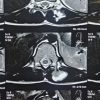

It was not associated with pain. There was no history of trauma to left shoulder. On examination, a hard and trans-illumination negative swelling, measuring 6*4*3 cm, was noted on the lateral aspect of left shoulder just below acromion process (Fig. 1). The swelling was non-mobile, non-tender, and non-adherent to overlying skin or muscle tissue. Skin over the swelling appeared normal. X-ray of the left shoulder showed irregularly ossified lesion on the lateral aspect of proximal humerus just below acromion process (Fig. 2) MRI was done and revealed a large, well defined, fairly well capsulated, and lobulated mass along lateral aspect of proximal humerus measuring 6*4*3.5 cm in size with a thin stalk connecting to postero-lateral corner of acromion process (Fig. 3). It showed multiple areas of extensive calcification with a very thin cartilaginous cap. Above said features defined a benign lesion but few peculiar signs of Exostoses. Hence, patient was posted for J needle biopsy which suggested bony trabeculae along with thin cartilage without dysplasia. As the lesion was benign, excisional biopsy was planned by direct lateral approach to proximal humerus and the mass was carefully separated from surrounding tissue with blunt dissection (Fig. 4).